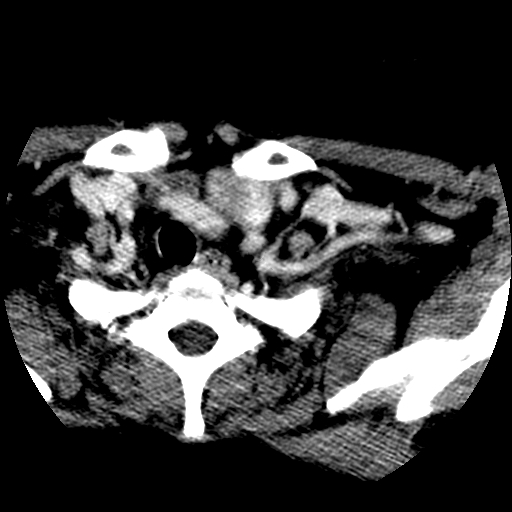

标题: CT25491:女,55岁,发现左侧甲状腺肿块一个月。 [打印本页]

女,55岁,发现左侧甲状腺肿块一个月,彩超示:甲状腺多发结节伴左叶结节液化。

考虑右叶结节性甲状腺肿,伴左叶钙化。主要(1)密度均匀,边境清。(2)病灶与血管界限清。

考虑左侧甲状腺结节性甲状腺肿,不排除甲状腺腺瘤。